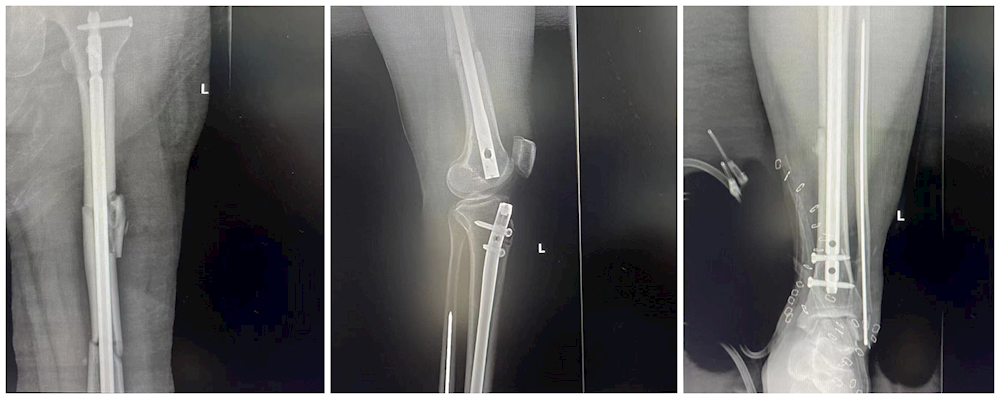

患者手术前左腿情况

患者手术后左腿情况

入院后,医生马上对刘阿姨的伤情进行检查,并对伤口进行消毒包扎,经初步诊断患者为左下肢多发伤、左股骨粉碎性骨折、左胫骨开放性粉碎性骨折、左腓骨粉碎性骨折、左胫骨远端粉碎性骨折、左跟骨骨折、左小腿、左踝、左足皮剥脱伤并部分损伤、左踝、左足背皮肤撕脱伤并部分缺损、左足第2-5跖骨远端骨折、头皮血肿,于是将刘阿姨生送入创伤骨科·手足显微外科做进一步治疗。

由于患者左下肢多发伤,多处骨折,手术难度非常大,创伤骨科·手足显微外科负责人唐继全立即开辟绿色通道并带领团队为患者制定最优、最有效的手术方案,在与患者家属沟通后,确定为患者先施行左小腿、左踝、左足创面清创+VSD负压引流+胫腓骨折复位克氏针内固定术+胫骨结节骨牵引术、石膏外固定术。待患者伤情稳定后再择期进行第二期、第三期手术。

经过一系列的术前准备与检查后,刘阿姨被送入手术室,手术由唐继全主刀,在手术室麻醉医师和护士的密切配合下,经过4个多小时的努力,手术成功,随即患者被送入ICU进行进一步治疗,随时密切关注患者情况。在医护人员的精确治疗和悉心护理下,患者病情稳定,转回普通病房,在术后第二周,第三周唐继全主任为患者成功施行后两期手术。目前患者术后恢复良好,已康复出院。